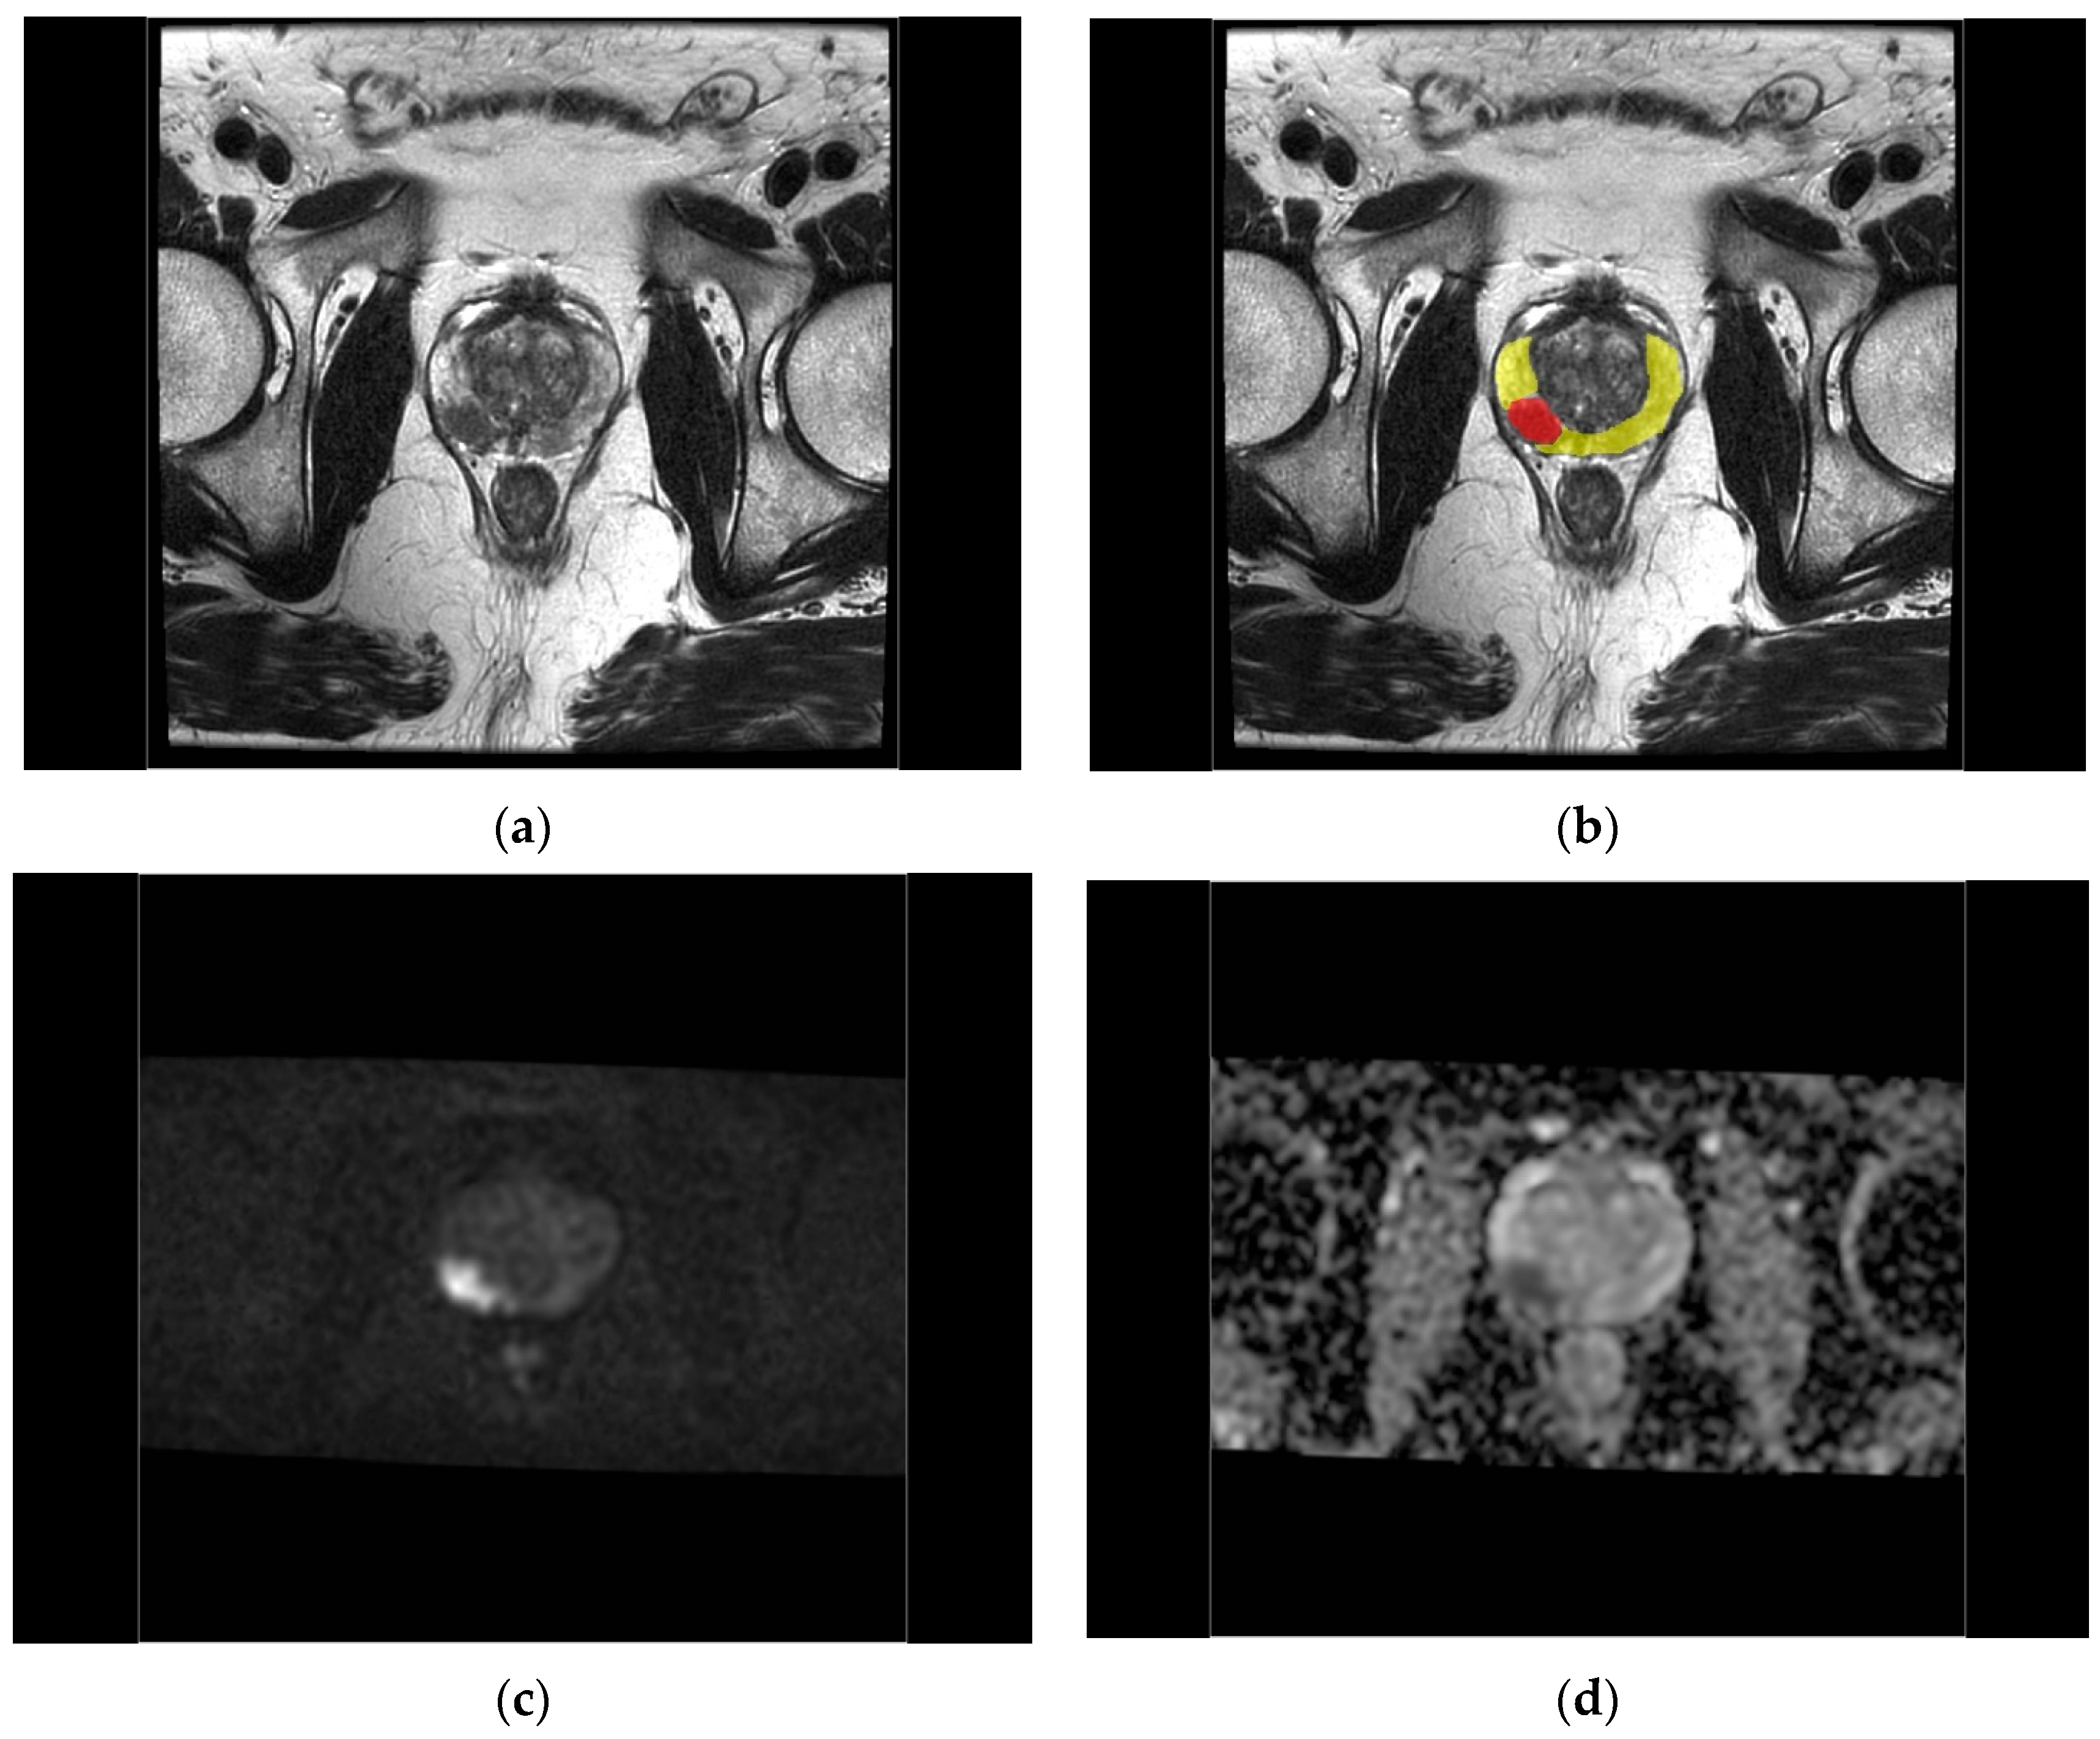

2.4. Region of Interest Definition

2.5. Radiological and Pathological Evaluation